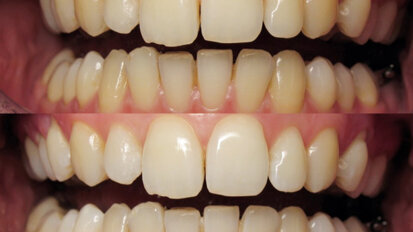

Bělení zubů a ortodoncie

St. 9. září 2020